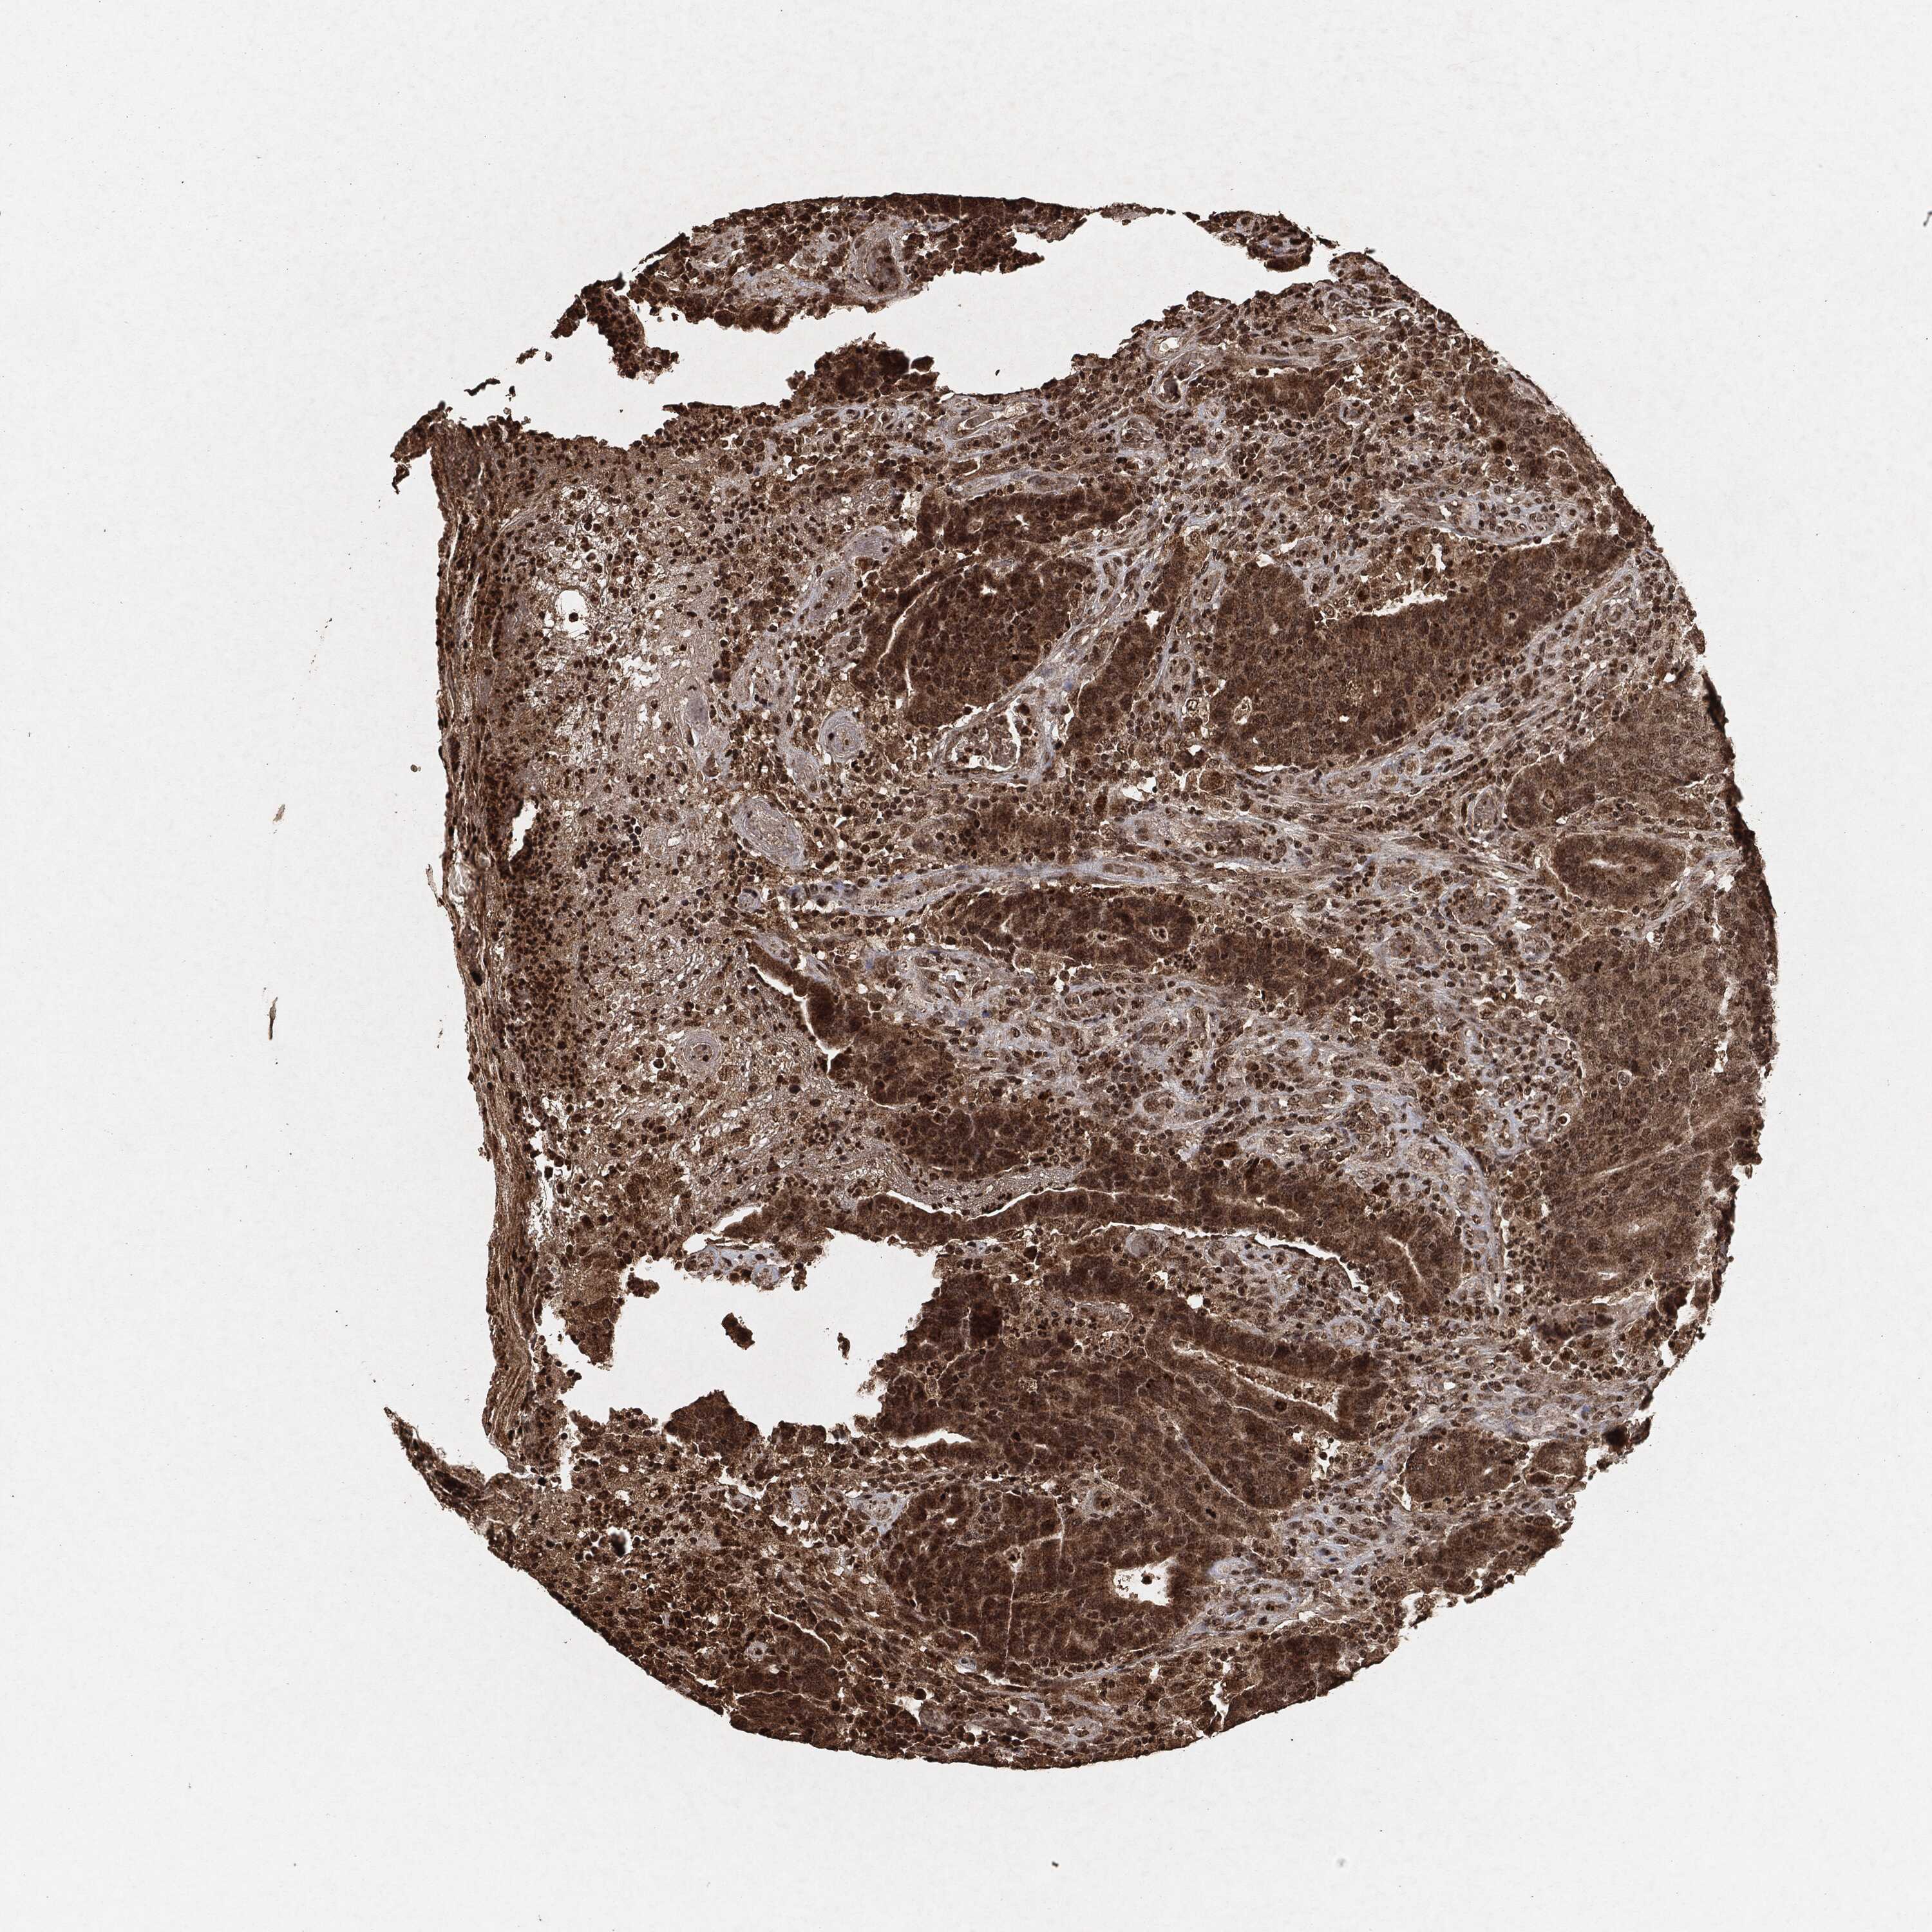

CANCER COLORECTAL CANCER Show tissue menu

Colorectal cancer

Human cancer

Colon adenocarcinoma